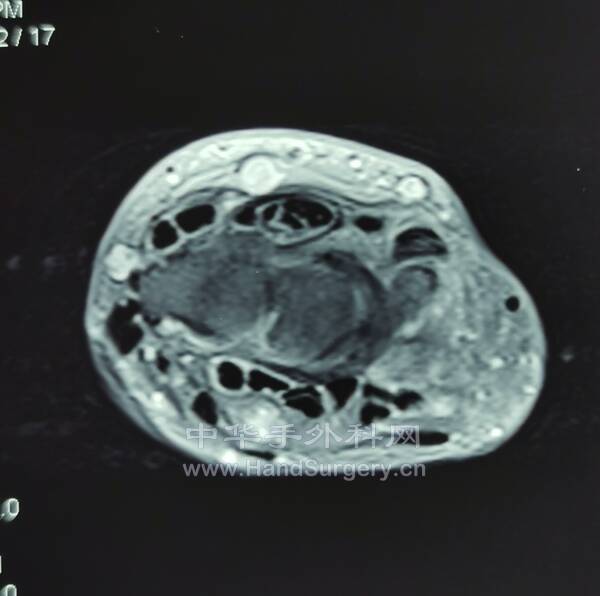

腱鞘巨细胞瘤(黄色素瘤)

沿郎格氏线设计切口